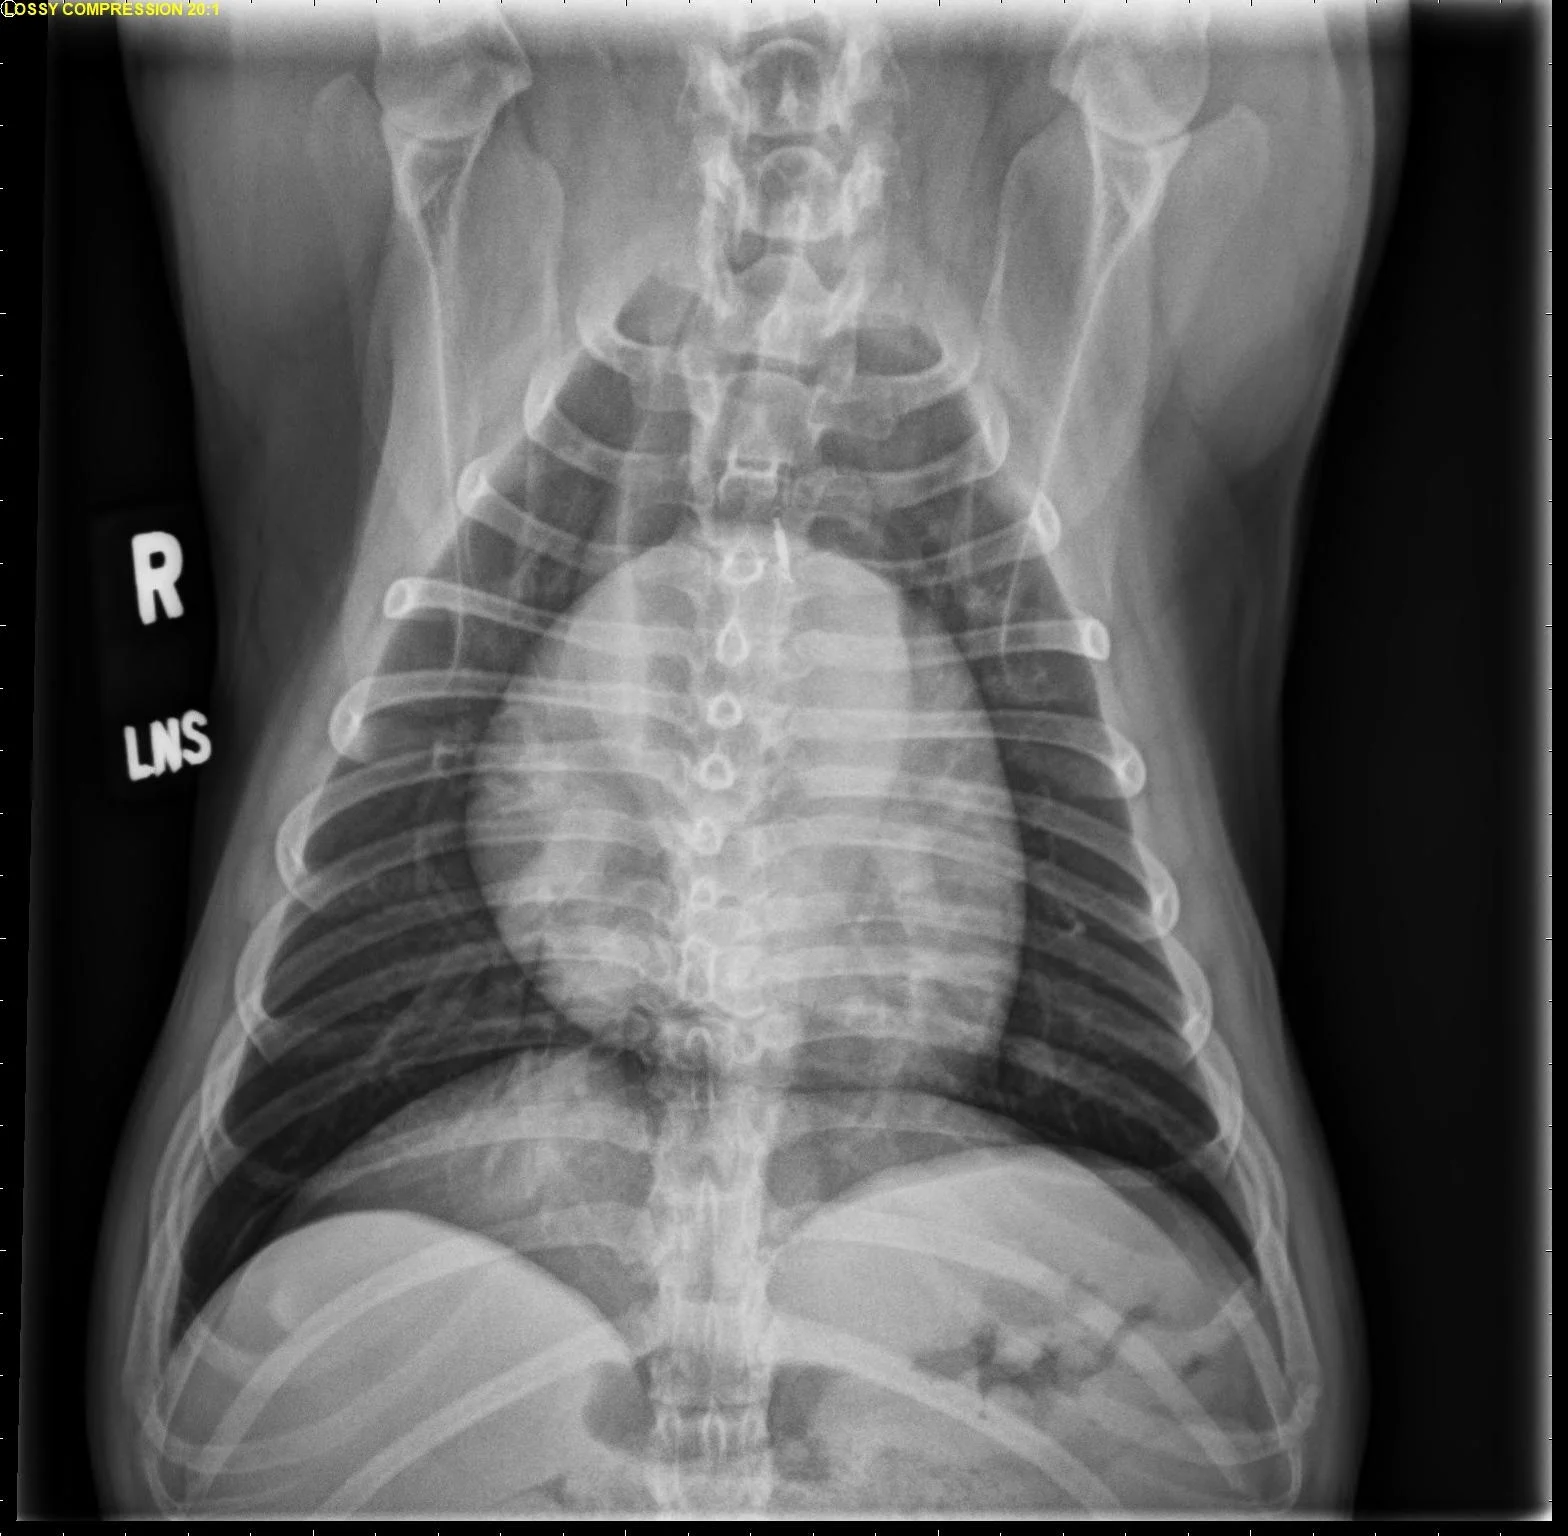

FIGURE 2 Normal DV (left) and VD (right) projections of the thorax in a large, crossbreed dog. The cardiac silhouette appears more rounded, and the caudal pulmonary vasculature is more apparent (arrowheads) in the DV view compared with the VD view. In some DV projections, the cardiac silhouette can appear significantly displaced to the left (not apparent in this case). Images courtesy of Federico Villaplana Grosso, DACVR, DECVR